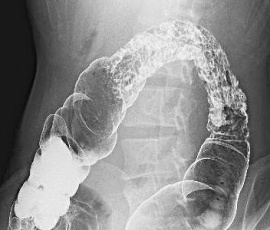

便潜血陽性にて精査目的に受診。腹部CT検査にて、脾弯曲部に限局した全層性炎症を疑う腸管壁の肥厚所見を認め、精査の結果、大腸クローン病と診断。内科的治療を継続したが、follow upの内視鏡所見で改善傾向がみられず、手術(腹腔鏡下結腸切除術)を施行。

透視画像